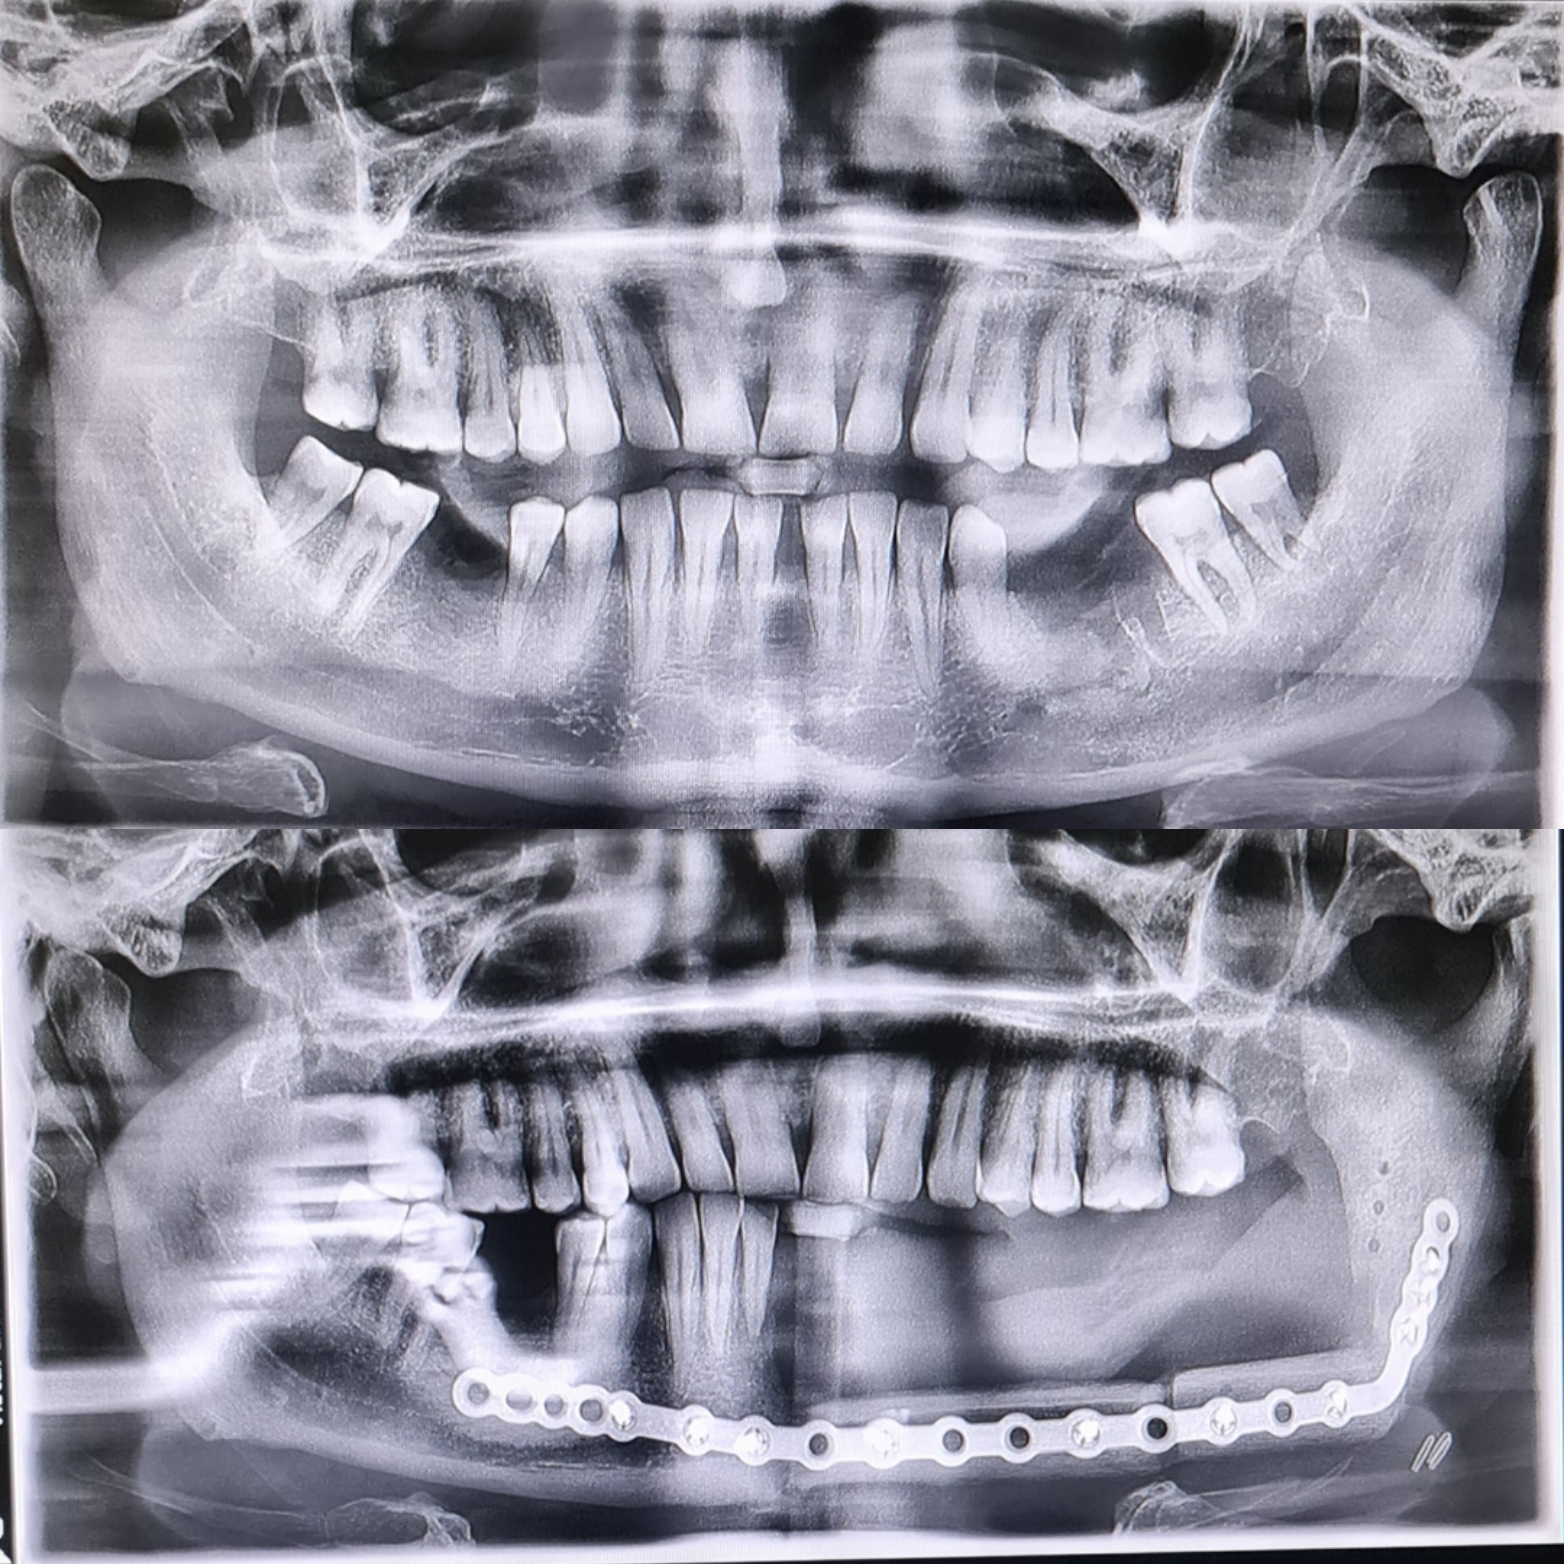

Fibula grefti ile alt çene rekonstrüksiyonu

Detaylı muayene, 3D tomografi ve yüz analizi ile cerrahi planlama.